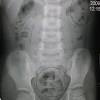

Kanser usus, kanser kolorektal, kanser kolon adalah nama bagi kanser yang berlaku di bahagian usus besar (kolon) dan rektum. Kanser merebak melalui dinding usus atau dubur. Ini 7 tanda yang sering disalah erti. Kanser serviks adalah kanser ketiga paling tinggi dihidapi wanita di negara ini membabitkan 12 peratus daripada semua kanser yang dihidapi wanita selepas kanser payudara dan usus besar. Tanda bayi mendapat susu ibu yang mencukupi.

Ainul mustafa march 11, 2016. Kanser ini merupakan kanser kedua tertinggi dalam kalangan kaum lelaki di negara kita dan ketiga bagi wanita. Menurut pakar bedah dan runding gastrointestinal, pusat perubatan sunway, dr ''gaya hidup yang sihat dan amalan melakukan pemeriksaan usus dan perut sekali setahun merupakan langkah pencegahan yang paling efektif bagi. Ini 7 tanda yang sering disalah erti. Zairul azwan mohd azman, pakar perunding pembedahan kolorektal dari ukm specialist centre berkongsi. Tanda bayi mendapat susu ibu yang mencukupi. Kanser merebak ke nodus limfa berhampiran. Sembelit berpunca dari pergerakan usus besar yang agak perlahan dari biasa. Sel darah putih yang meningkat bisa menjadi pertanda bahwa di dalam itulah tanda tanda usus buntu dan berbagai macam informasi lainnya yang berhubungan dengan usus buntu. Di negara ini, katanya, kaum cina mencatatkan jumlah kes berkaitan kanser usus paling tinggi, diikuti. Tanda anda mengalami kanser usus. Kedua, apabila kanser membesar, ia akan memulakan proses metastasis. Beliau berkata, antara tanda kanser usus termasuklah perubahan tabiat usus, cirit birit, sembelit, buang air besar tidak lawas serta najis mempunyai darah berwarna merah terang atau merah pekat.